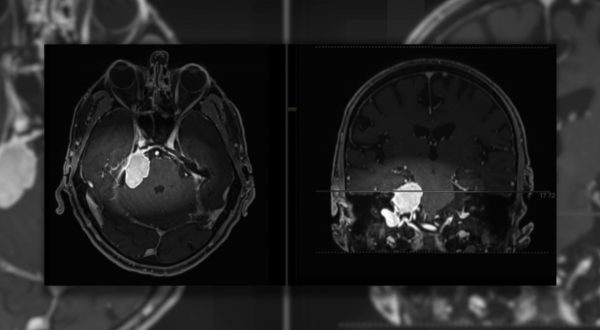

Meningiomi, i sintomi da tenere d’occhio